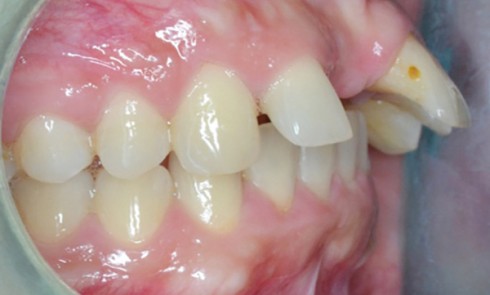

Examen clinique Sur le plan exobuccal (fig. 1 à 2), la patiente présente un profil sous-nasal concave, une birétrochéilie et une bascule...